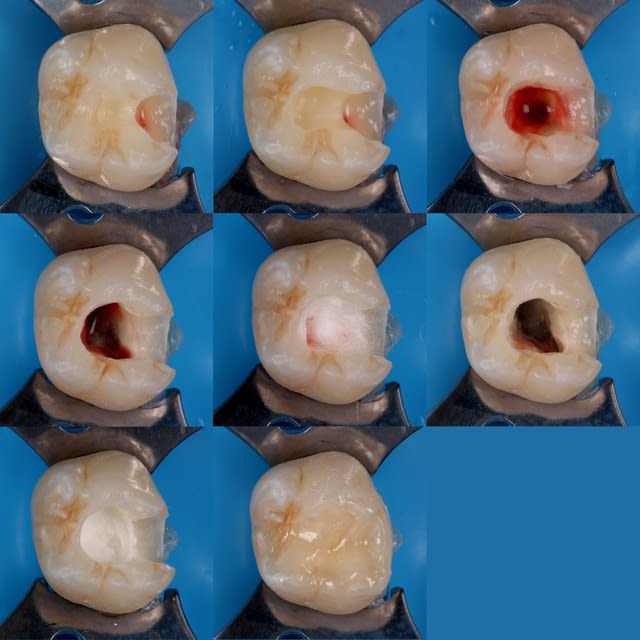

Peu de temps après, il fait une exposition pulpaire sur une 26 présentant une carie pourtant à peine dentinaire. L'exposition baigne dans la salive, la digue n'est pas posée, contrairement aux consignes du service. "Gentil", j'explique que l'exposition était évitable et constitue un mauvais facteur pour le pronostic de la dent, d'autant plus au vu de la contamination salivaire. Faciès bovin, aucune réaction. J'explique en d'autres termes : "Tu vois cette petite fille de 7 ans ? Tu comprends que sa 26 est probablement perdue au long terme par ton acte ?". Aucune réaction. J'insiste et lui demande sincèrement : "Ça ne te fait rien ? Tu ne te sens pas un peu triste ?". Il répond nonchalamment : "J'sais pas, faut qu'j'aille chercher une digue, c'est ça ?".

Img 8798  2  kdehll - Eugenol

Pulpo11 rfxfdi - Eugenol

Img 8920  2  lqxvfg - Eugenol

De deux, tu penses que ton iconographie m'impressionne? Il n'y a rien de très compliqué.

Je suis vraiment content que tu me dises ça. Cette iconographie me demande énormément de temps sur des enfants de 4-6 ans et dans le flux d'un cabinet libéral. Comme ce n'est "pas compliqué" et que tu as plein de conseils pour les enseignants, tu va pouvoir m'aider à préparer les cours ?